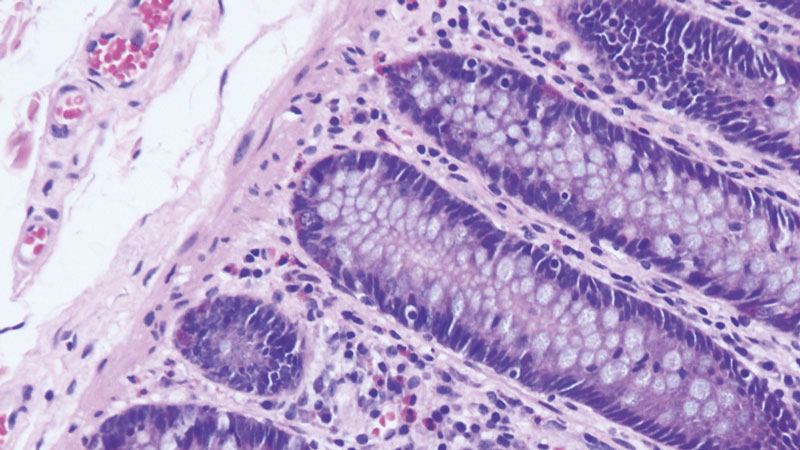

Τα αναλώσιμα Αιματοξυλίνης-Ηωσίνης είναι έτοιμα προς χρήση αντιδραστήρια που παρέχουν εξαιρετική ποιότητα χρώσης και επαναληψιμότητα χρησιμοποιώντας το μηχάνημα Dako CoverStainer. Όλα τα αντιδραστήρια είναι πλήρως συμβατά και μπορούν να εισαχθούν απευθείας στο σύστημα ελαχιστοποιώντας τον χειροκίνητο χρόνο. Το μέσο τοποθέτησης και η καλυπτρίδα μειώνουν τον κίνδυνο εμφάνισης φυσαλίδων αέρα παρέχοντας έτσι διαυγή τμήματα ιστών αιματοξυλίνης-ηωσίνης. Η βάση πλακιδίων του Dako CoverStainer έχει μοναδικό σχεδιασμό που ελαχιστοποιεί τη μεταφορά αντιδραστηρίων, επεκτείνοντας τη μακροζωία του αντιδραστηρίου και επιτρέποντας συνεπή αποτελέσματα χρώσης ενώ ταυτόχρονα επιτρέπει πλήρη προβολή των πλακιδίων, γεγονός που βοηθάει να μειωθεί ο χρόνος που αφιερώνεται στη διαλογή τους. Τέλος, διατίθενται καλυπτρίδες ποιότητας σε διαφορετικά μεγέθη που κυμαίνονται από 24 mm πλάτος x 40-60 mm μήκος.